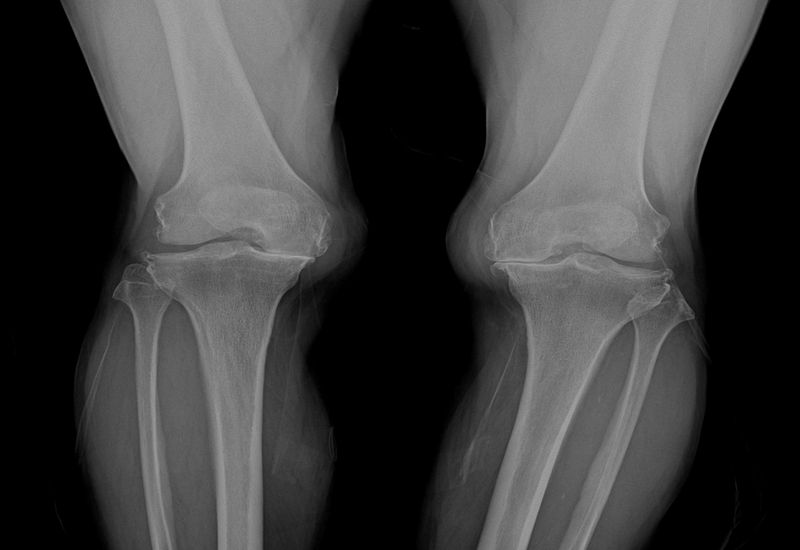

사용 목적은 무릎 통증 경감이며 ▲방사선학적으로 확인된 골관절염 2~4단계 환자 가운데 ▲진단적 신경차단술에서 통증이 50% 이상 줄어드는 반응을 보이고 ▲6개월 이상 약물치료를 포함한 보존적 치료에도 호전이 없는 경우에 시술할 수 있다.

무릎 퇴행성 관절염을 오랜 기간 앓게 되면 관절 내 염증 물질들이 연골이나 뼈는 물론이고 무릎 주변의 신경에 염증을 유발하여 통증의 역치가 낮아지게 된다.

때문에 퇴행성관절염이 없는 사람에 비해 작은 자극에도 통증을 느끼기 쉽다.